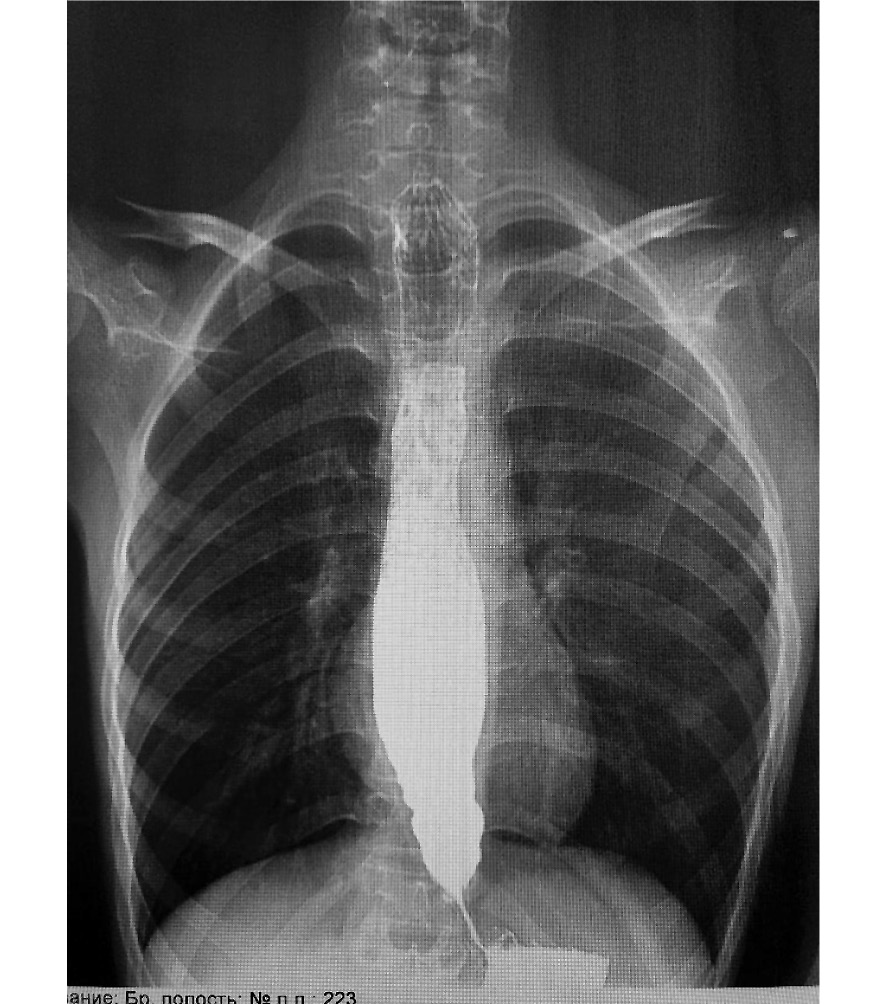

Всем пациентам диагноз был поставлен на основании клинических данных и дополнительных методов обследования. Клинические данные включали жалобы и срок заболевания. Основными методами обследования, которые подтвердили диагноз, являлись эзофагогастродуоденоскопия (ЭГДС) (рис. 1) и эзофагография (рис. 2).

Рис. 1. Эзофагогастродуоденоскопия: эзофагит и выраженное сужение пищевода.

Fig. 1. Esophagogastroduodenoscopy: esophagitis and narrowing of esophagus.

Рис. 2. Контрастная эзофагография: расширение пищевода, симптом «птичьего клюва».

Fig. 2. Preoperative esophagogram, showing dilating esophagus and “Beak sign”.

- контрастной эзофагографии, которая выявила характерные рентгенологические признаки АП: значительное расширение просвета пищевода, наличие в пищеводе остаточного содержимого, отсутствие отчётливого газового пузыря в желудке и признак «птичьего клюва»;

- ЭГДС, на котором выявлено стойкое сужение кардиального жома, ослабление перистальтики пищевода, отсутствие расслабления НПС и сужение пищевода на уровне НПС;